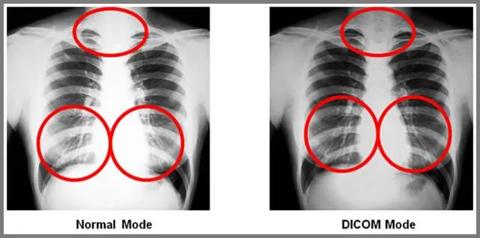

Subtle details in medical images are more visible when the image is DICOM calibrated.